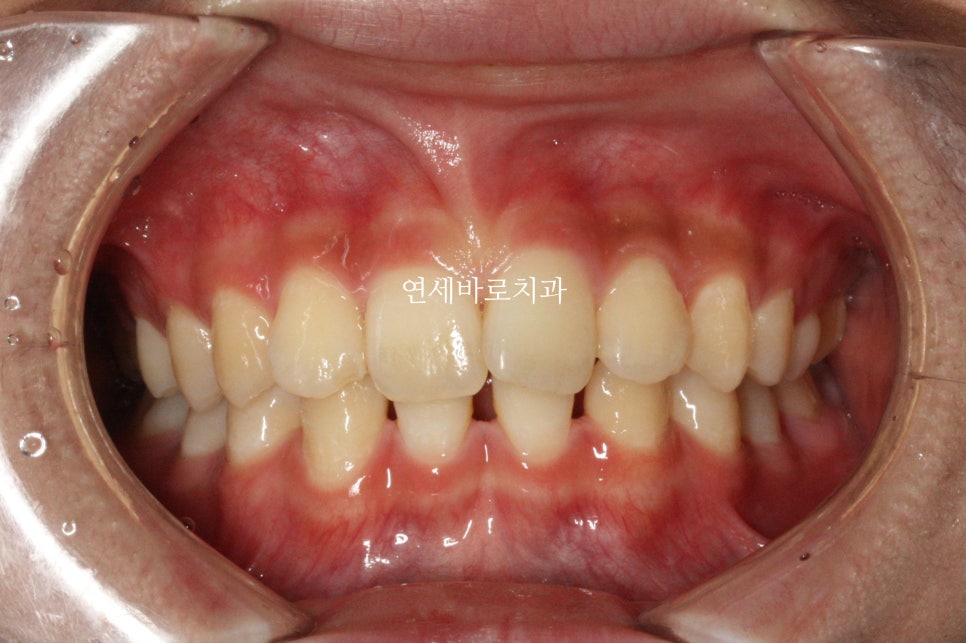

이 친구는 약간의 돌출도 보이고 있었기 때문에 위쪽 치아를 두개 발치했었습니다.

약2년의 치료기간이 걸렸으며 올해 초에 정기검진을 왔습니다

치료가 끝난지 약 3년정도 지난 모습인데 긴밀한 교합으로 인해 치료결과가 잘 유지되고 있는 것 같습니다.